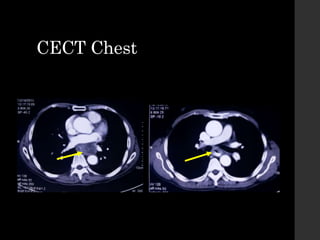

CECT Chest

Collapse

Pleural

effusion